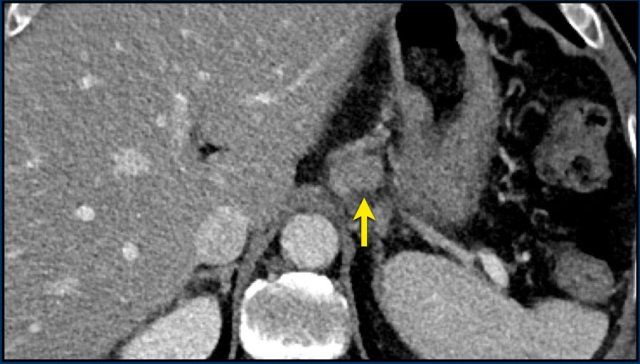

mRECIST for Hepatocellular carcinomas

Tumour response assessment based on changes in size alone can be deceptive when applied to hepatocellular carcinoma (HCC) treated with targeted or interventional therapies.

In 2000 the European Association for the Study of the liver (EASL) assembled an expert panel on HCC which suggested that the optimal method for treatment response assessment in HCC should be the estimation of viable tumour with contrast enhanced imaging.

These new criteria were based on RECIST 1.1 and referred to as modified RECIST (mRECIST) with the most important feature of defining viable tumour as uptake of contrast agent during arterial phase dynamic imaging on CT or MRI.

mRECIST is only used for typical lesions showing intratumoral arterial enhancement, while RECIST 1.1 is applied for atypical enhancing lesions and extrahepatic disease.

The CT image of the liver of a 96-year-old male with HCC in the late arterial phase shows a hypervascular tumour in the right liver lobe (arrowheads).

The tumor is well delineated from the surrounding parenchyma.

In the portal-venous phase the HCC is hardly distinguishable from the liver parenchyma due to early washout of contrast.

This HCC is suitable for mRECIST.